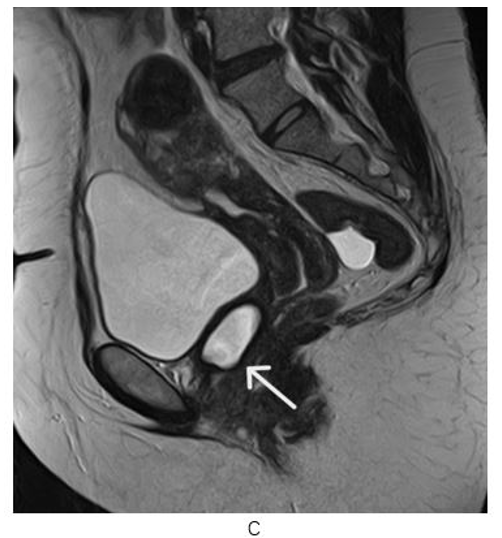

Figure 3: Pelvic MR Non-Enhanced Sagital T2 (C) image : Cystic Structure with Regular Contours at the Left Anterolateral Wall of the Proximal 1/3 Part of the Vagina ( White Arrow)